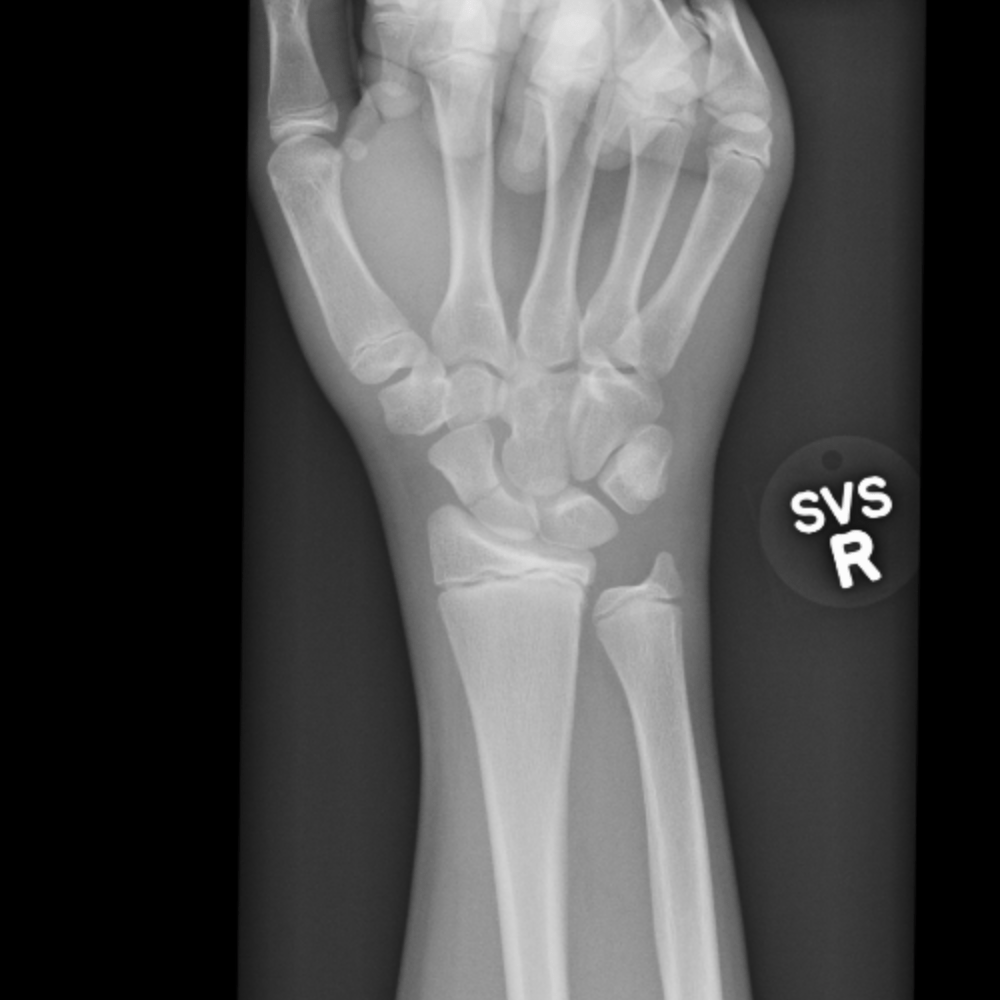

Fractures through the scaphoid bone) are common, in some instances can be difficult to diagnose, and can result in significant functional impairment. Performing rehabilitation exercises after suffering a scaphoid fracture can help you retain full function and mobility in your wrist.

Of (2a) despite immobilization, a fracture line through the scaphoid waist (arrow) remains visible. If the scaphoid fracture is not showing enough evidence of healing, rom may be delayed. Symptoms can include pain and swelling around the wrist. Scaphoid fractures can be mistaken for wrist sprains because they have similar symptoms. A delay in the diagnosis and treatment of a scaphoid fracture may alter the prognosis for union, increase the risk of avascular necrosis, and. Distal radius fractures programme online course: Scaphoid fractures most often occur in males between the ages of 15 to 30 years old and usually are sustained with wrist hyperextension and radial deviation as a individuals with a scaphoid fracture often present with pain, swelling, decreased range of motion, and tenderness in the anatomic snuffbox. Frequently, however, the diagnosis of this scaphoid injury is delayed; Rehab and return to sport treatment of acute scaphoid fracture in the athlete depends on: Scaphoid fracture | faqs answered. A scaphoid fracture is the most common type of carpal fracture affecting young active people. By dr arun pal singh. Treatment may involve surgery to prevent the risk of nonunion. A scaphoid fracture is an injury to one of the small bones in the wrist. The scaphoid bone is a small bone located at the base of the thumb next to the radius, one of the bones in the lower arm. A scaphoid fracture is a type of wrist fracture that occurs most commonly from a fall on the outstretched hand. Scaphoid fractures are an important public health problem as they predominantly affect.